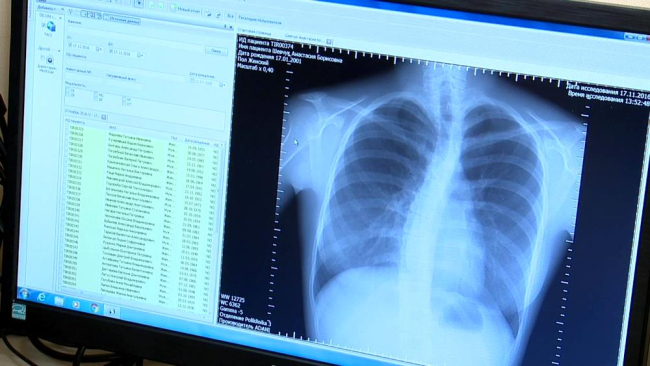

Тирасполь, 18 ноября. / ИА «Новости Приднестровья»/. В столичной поликлинике №3 начал работу современный флюорографический аппарат. Работающий на цифре он превосходит своего аналогового предшественника по всем параметрам – и по скорости, и по качеству картинки. Первое достигается за счёт практически моментального получения снимка – без необходимости проявления плёнки и использования химреактивов. Он заносится в электронную базу, историю болезни пациента и, в случае необходимости, может пересылаться другому врачу. Качество – тоже несравнимо со старым.

«Можно сразу увидеть снимок, выделить нужную область, сделать снимок более или менее контрастным. Это, конечно, гораздо более удобно по сравнению с плёночными мелкокадровыми снимками. Там был задействован процесс химической обработки, могли появляться дефекты», – рассказала заведующая рентгенотделением Светлана Звягина.

«Улучшилось выявление туберкулёза, онкопатологий и других заболеваний верхних дыхательных путей на ранних стадиях. Это тоже большой плюс», – отметил и.о. министра здравоохранения Александр Гончар.